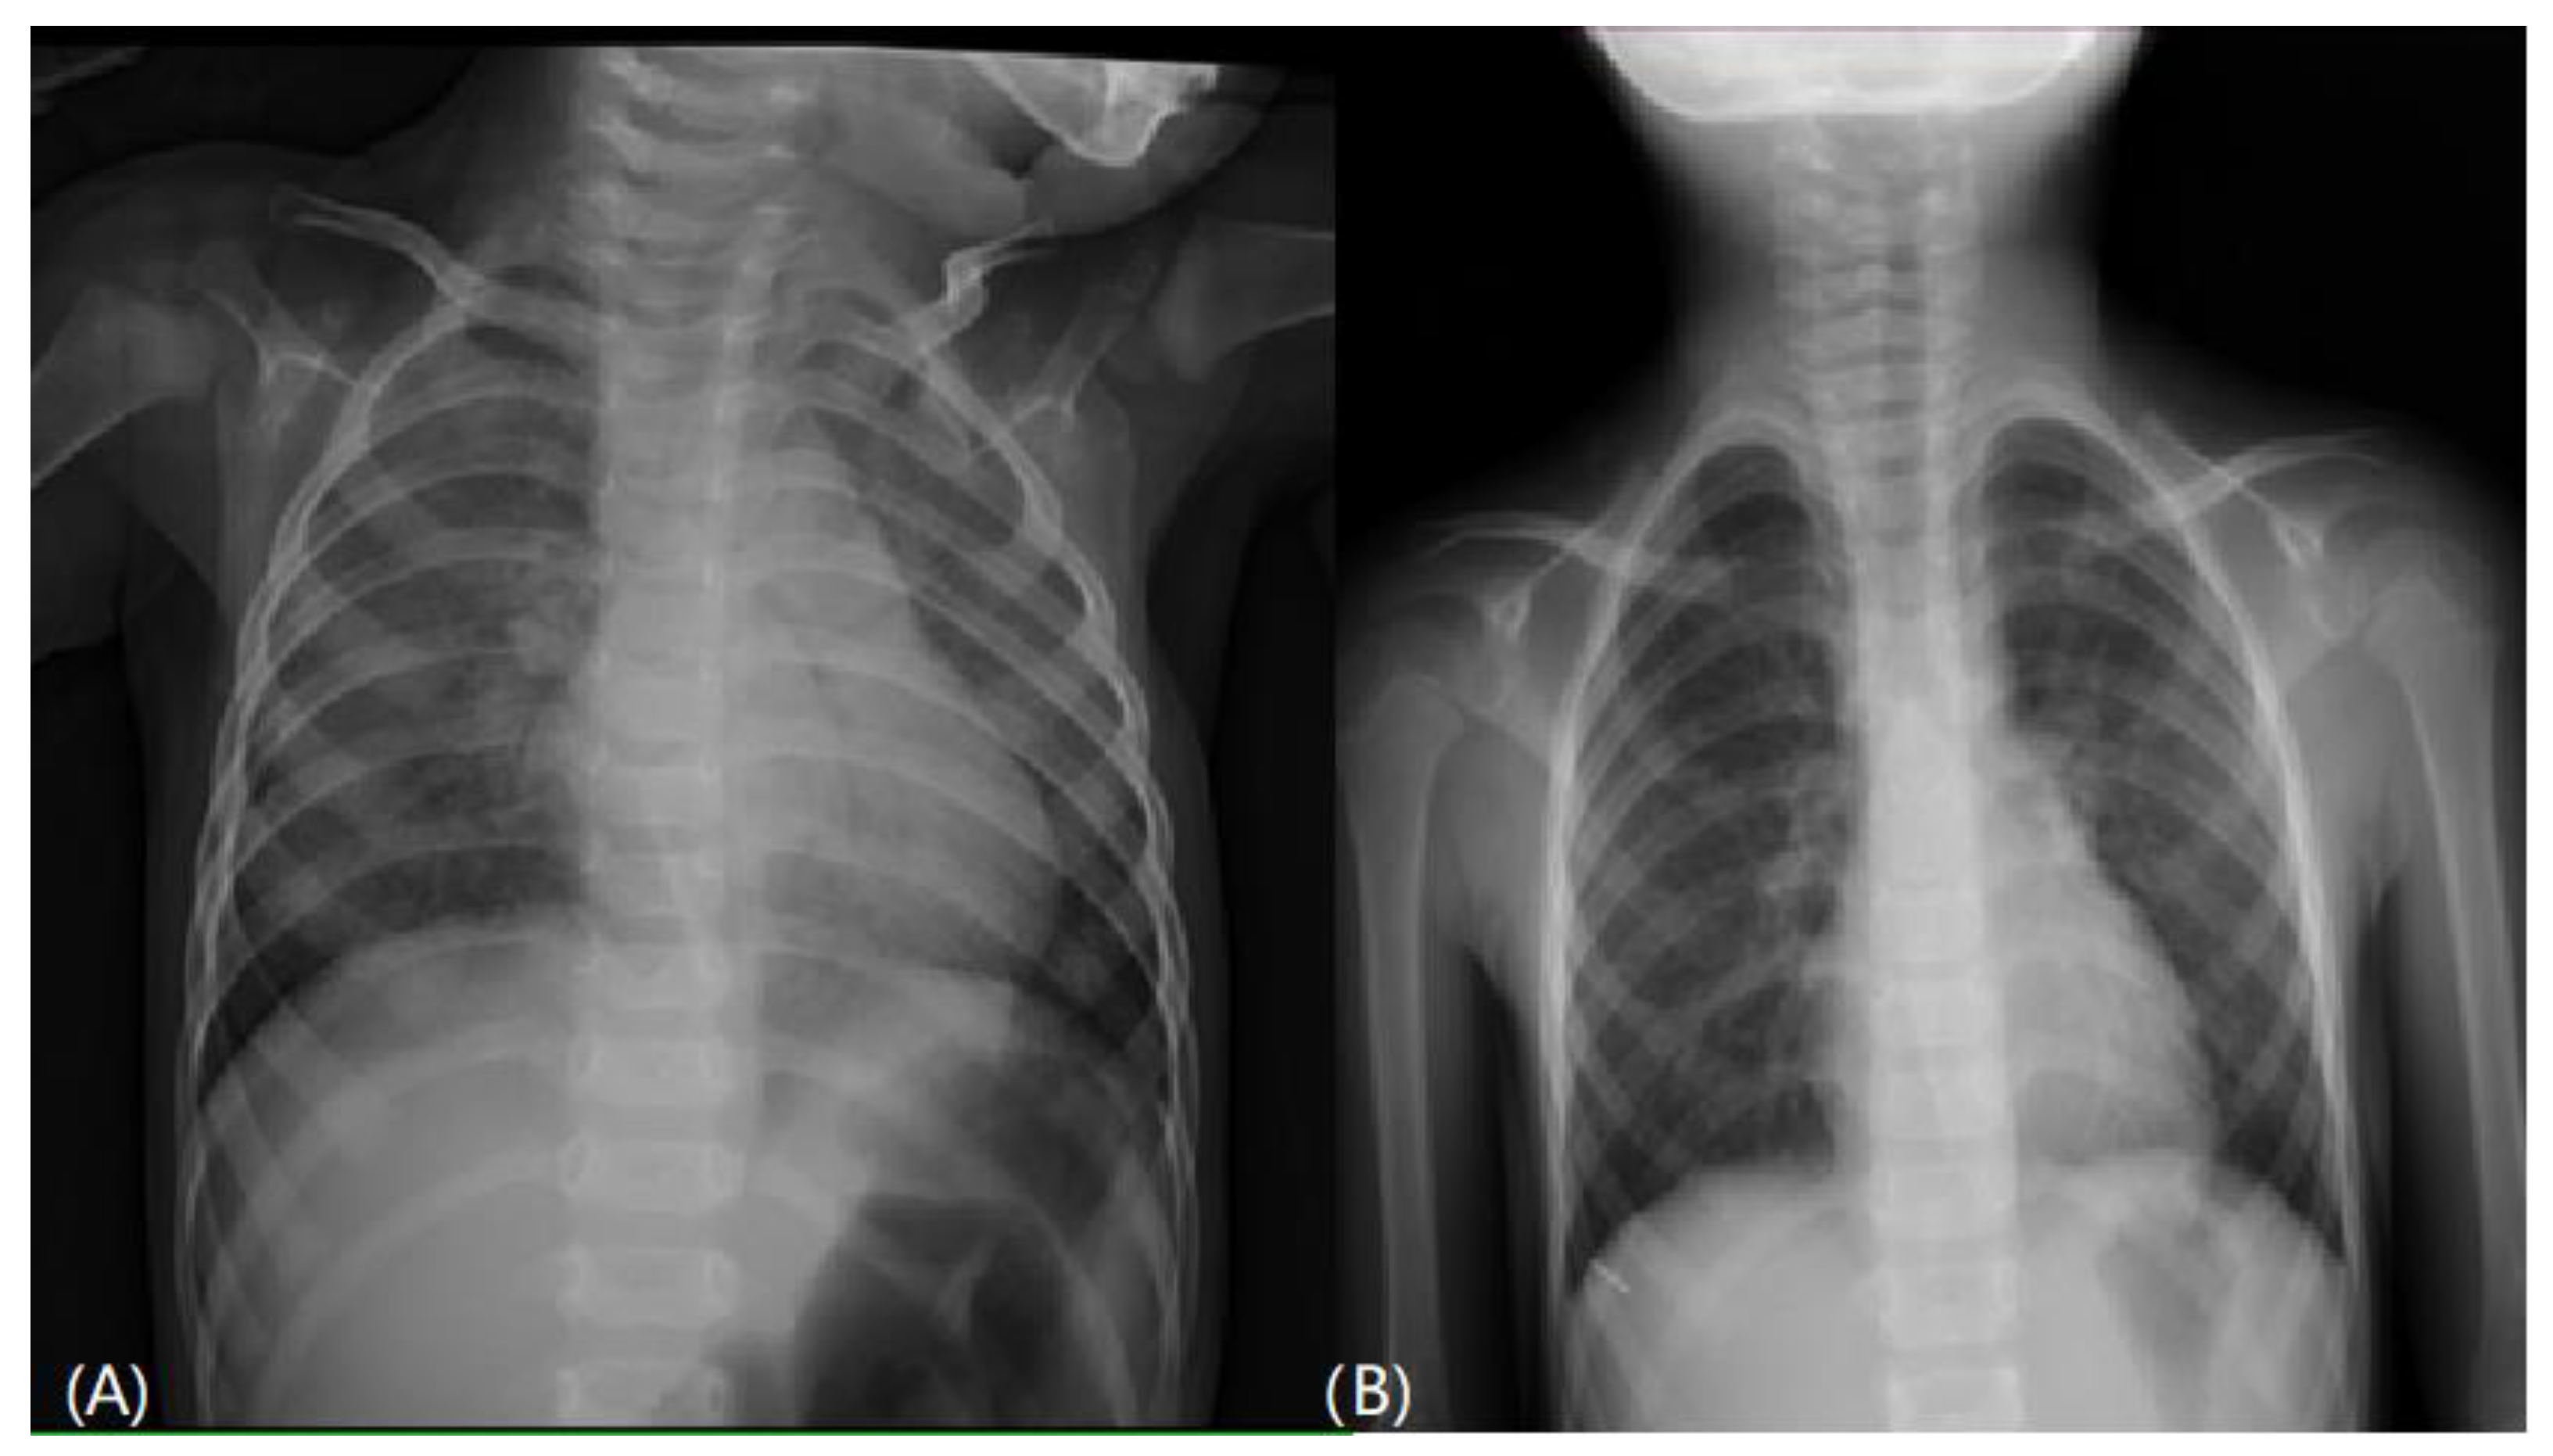

From www.mdpi.com

Children Free FullText Congenital Surfactant C Deficiency with Baby Chest Heaving when your baby is wheezing, they might take tiny breaths accompanied by a whistling sound. signs that children are struggling to breathe. respiratory distress is a clinical condition characterized by the presence of one or more signs of increased work of breathing. newborn respiratory distress presents a diagnostic and management challenge. Because of a baby’s small. Baby Chest Heaving.

From radiologyassistant.nl

The Radiology Assistant Neonatal Chest XRay Baby Chest Heaving signs that children are struggling to breathe. respiratory distress is a clinical condition characterized by the presence of one or more signs of increased work of breathing. newborn respiratory distress presents a diagnostic and management challenge. Watch the videos and know the signs and the different noises pēpi. Newborns with respiratory distress commonly. when your baby. Baby Chest Heaving.